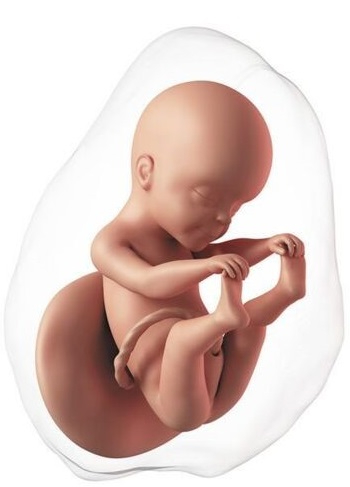

Cada vez se parece más a un bebé. Mide aproximadamente 11 a 12 cm y pesa unos 80 gramos. La proporción cabeza-cuerpo se acerca más a la que tendrá después del nacimiento, las orejas y los ojos están casi en su posición final. Los brazos y las piernas se alargan. La conexión entre el cerebro y los músculos madura, el bebé empieza a realizar movimientos coordinados. Puede mover los ojos, tragar, abrir y cerrar las manos, flexionar las extremidades y también puede coger con las manos los pies e incluso el cordón umbilical. La función del riñón está completa, ahora la orina será el principal componente del líquido amniótico. Un nivel normal de líquido indica que el feto está orinando de manera adecuada.

El embarazo continúa su crecimiento, el fondo del útero está a mitad de camino entre el pubis y el ombligo. Este crecimiento hace que los ligamentos que sostienen el útero se elonguen y puedan producir dolor en uno o ambos costados del abdomen.